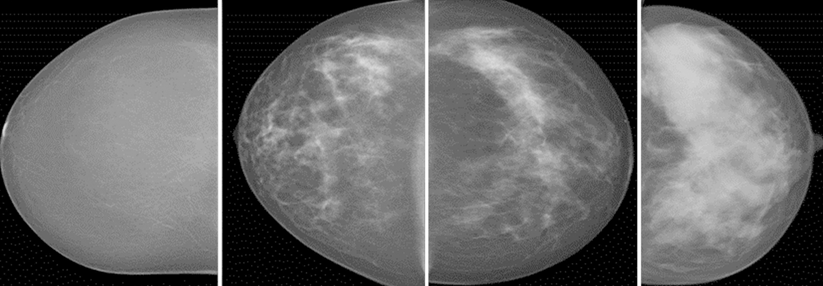

Neue Studiendaten deuten darauf hin, dass Brustkrebs Patient:innen von dem neuen gegen HER3 gerichteten ADC Patritumab-Deruxtecan profitieren. Neue Studiendaten deuten darauf hin, dass Brustkrebs Patient:innen von dem neuen gegen HER3 gerichteten ADC Patritumab-Deruxtecan profitieren. © Nadiia – stock.adobe.com